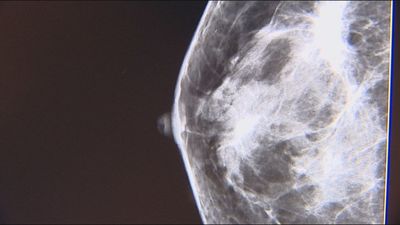

Confirman la eficacia de la inteligencia artificial en el diagnóstico del cáncer de mama Confirman la eficacia de la IA en el diagnóstico del cáncer de mama 16/03/2023